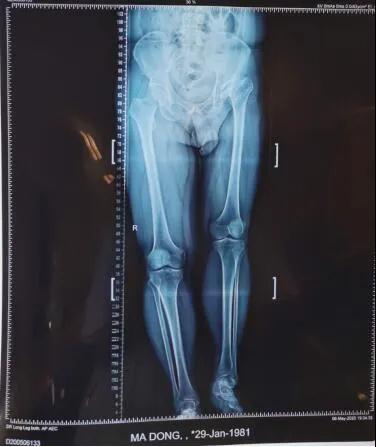

19日,beat365中文在线官网第六附属医院骨病矫形外科主任李璐兵向记者透露:预计3个月后,有望像正常人一样自如行走。当日,记者在病房走廊看到,马先生手扶助行器,正在练习行走。“17日手术的,今儿就可以下地了。”马先生说。39岁的马先生,年幼时就患有左髋化脓性关节炎,因当时治疗条件有限,造成后期左髋关节骨质破坏严重,左下肢比右下肢短缩了6厘米,走路时跛行很明显,加上左髋关节因为骨质破坏严重导致活动范围受限,就连穿袜子都需要别人帮助。

整个手术进行了两个小时,将置换后的髋关节假体准确复位,为患者重建了髋关节并且矫正两条腿基本恢复等长。

“人工关节置换手术的最大好处在于能够术后消除病变关节疼痛,大大改善关节功能,提高患者生活质量。” 李璐兵说,功能训练后,可以像正常人一样自如行走了。